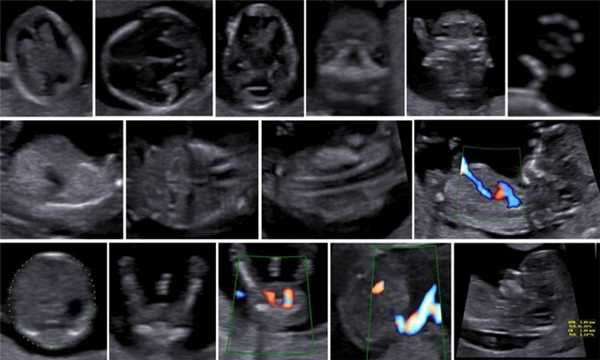

Описанные в литературе величины частоты выявления дефектов в I триместре беременности значительно различаются в зависимости от изученных популяций, методов и периодов [5]. По мере развития методов ультразвуковой диагностики усовершенствовался и анатомический анализ для I триместра беременности. Международное общество по применению УЗИ в акушерстве и гинекологии (International Society of Ultrasound in Obs tetrics and Gynecology - ISUOG) в 2013 г. предложило руководство для клинической практики, предполагающее проведение оценки анатомии плода между 11 нед 0 дней и 13 нед 6 дней беременности (рис. 3) [6].

Метод УЗИ позволяет выявлять в I триместре ряд аномалий развития плода:

- Видимые аномалии - анэнцефалия, алобарная голопрозэнцефалия, гастрошизис, омфалоцеле, аномалия предшественника аллантоидного стебелька, гидронефроз и некоторые несовместимые с жизнью остеохондродисплазии.

- Невидимые аномалии мозга, пищеварительной системы, урологические и скелетные аномалии.

- Некоторые аномалии, требующие анализа, - аномалии сердца, лица, конечностей, spina bifida.

Не так давно качество УЗИ в I триместре удалось повысить до уровня, позволяющего при рутинном ультразвуковом скрининге проводить полноценное диагностическое УЗИ. Достижения 3D/4D-методов и автоматизированные технологии измерения обеспечивают дополнительные возможности проведения точной анатомической оценки.